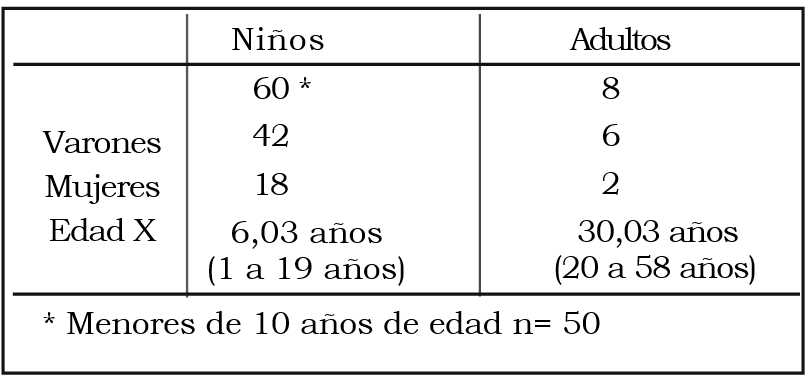

Se analizan los resultados obtenidos en 60 niños y 8 adultos con diagnóstico de epilepsia extratemporal operados entre 1988 y 1998 con un seguimiento mayor de 2 años. Todos fueron estudiados con TAC e IRM y EEG de cuero cabelludo. La Videotelemetría, ECoG intraoperatoria y la PESS se utilizaron de acuerdo con las necesidades de cada caso. En los niños se efectuaron 24 lesionectomías, 25 desconexiones, 7 polectomías y / o lobectomías, 1 hemisferectomía y 3 corticectomías. En los adultos se efectuaron 1 lobectomía, 4 corticectomías y 3 lesionectomías. De acuerdo con los criterios de Engel, en los niños los resultados fueron: 40 clase I, 5 clase II y 4 clase IV. En los adultos los resultados fueron: 4 clase I, 2 clase II, 1 clase III y 1 clase IV. Se excluyeron 11 pacientes con callostomías por no poder aplicar los criterios de Engel.

MATERIAL Y MÉTODO

Entre junio de 1988 y abril de 2000 fueron operados por epilepsia refractaria 178 pacientes; de éllos 75 niños y 14 adultos padecían epilepsias extratemporales (EE). Se incluyen pacientes operados hasta junio de 1998, con un seguimiento no menor de 2 años. Se excluyen los pacientes a quienes se realizó callosotomía, con diagnóstico de síndrome de Lennox-Gastaud. La indicación de la cirugía en estos pacientes fue con criterio paliativo y dirigida especialmente al control de las caídas que padecían. En ellos no pueden aplicarse los criterios de Engel. (Tablas 1, 2 y 3).

Tabla 1. Población